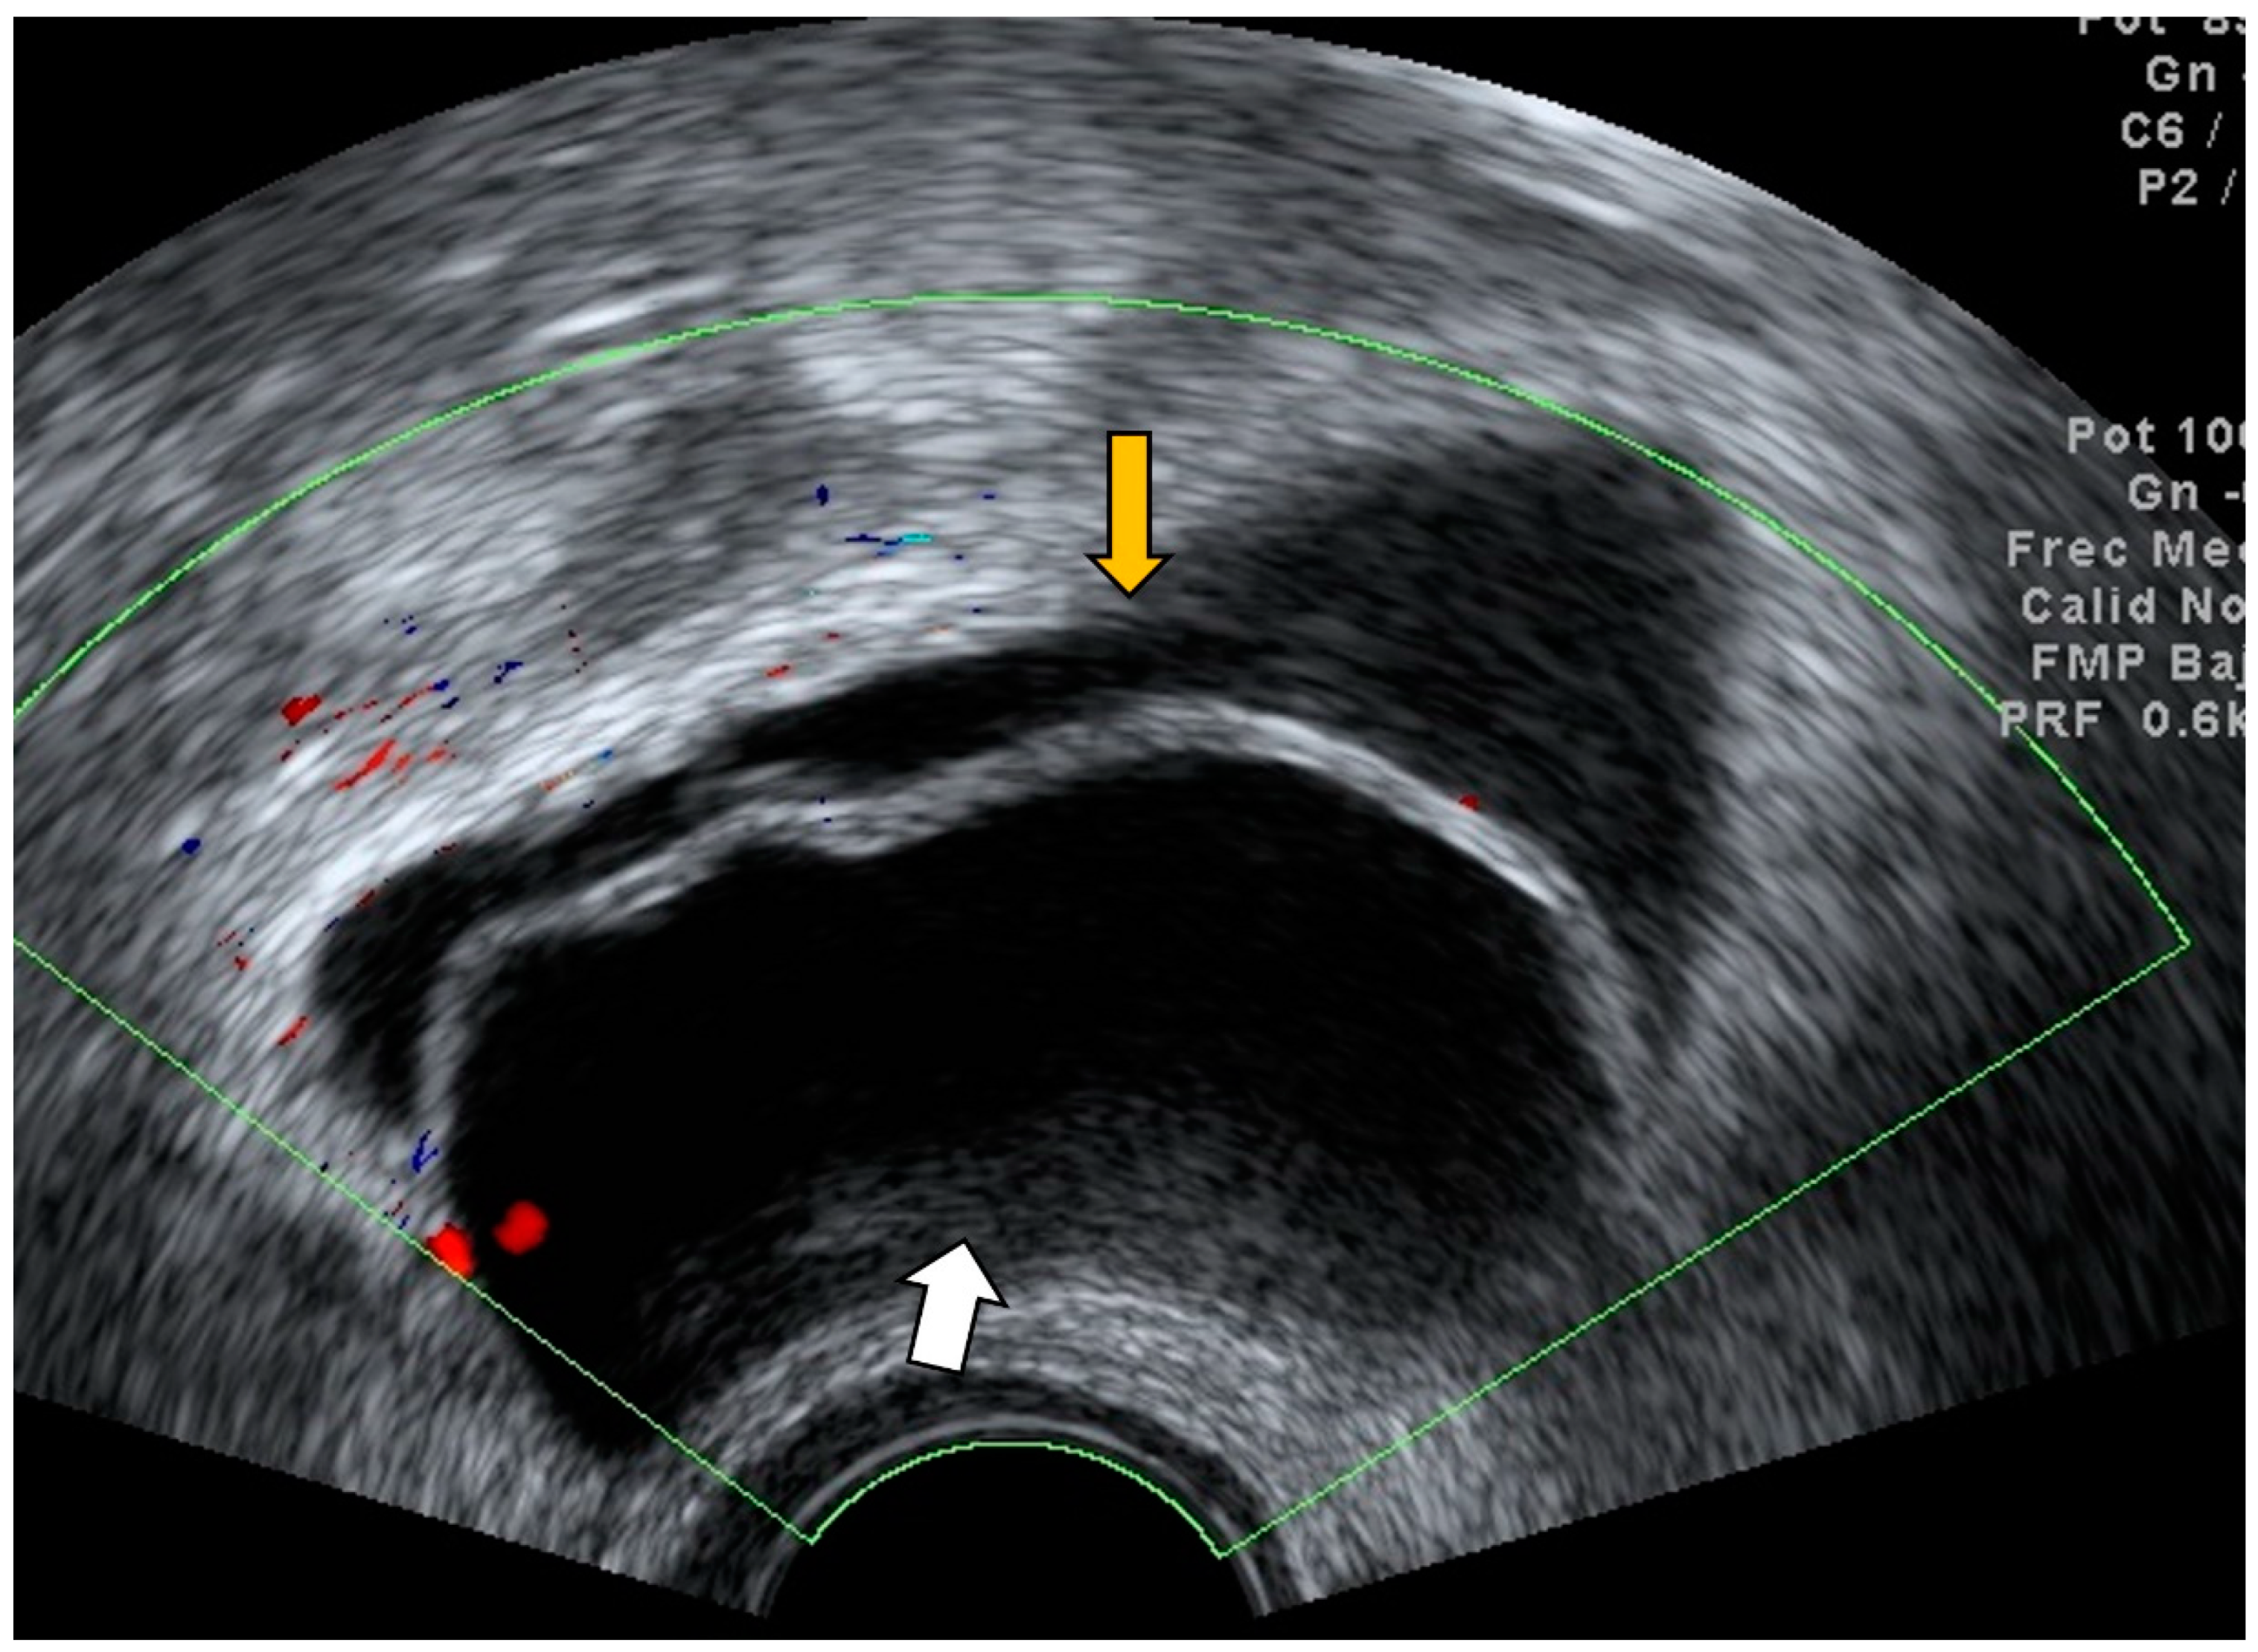

4.2. Thrombosis